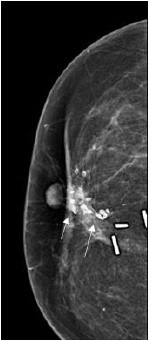

Linear and fine linear branching

As the name suggests they are fine, linear, thin, and irregular measuring < 0.5mm. They appear sometimes as discontinuous calcifications, as well as in a branching pattern, developing due to the filling in of the lumen of a duct/ducts which are involved by carcinoma. They have the highest positive predictive value amongst the suspicious calcifications (70%). They are categorised as BIRADS 4C [5]; (Figure 15).

Figure 15:RCC view of a 61-year-old woman showing linear calcifications (long arrows). Image Courtesy: HCG Hospitals, Bangalore.